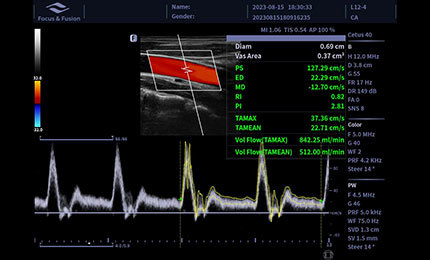

Auto Volume Flow

Urządzenie umożliwia pomiar obszaru naczynia krwionośnego, automatyczne określenie prędkości przepływu krwi w oparciu o analizę widmową oraz prezentację wyników objętości przepływu.